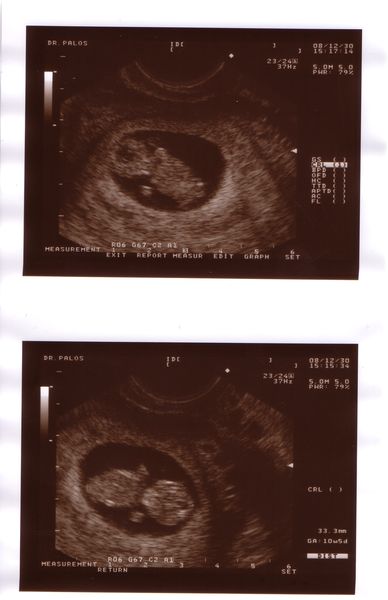

Ma vagyunk 10 hetesek, voltam 29-én ultrahangon, dobogott a szívecskénk, kaptunk képet is. 2,5 cm-es volt a picur. Január 21-én megyek integrált tesztre a Mátyásföld Klinikára. Volt már ott valaki? Akkor leszek 12 + 5 napos. Aki ilyen integrált teszten átesett, mesélne róla?

Küldöm a fotót, remélem látjátok rajta a lényeget, meg is fordítottam!

Baba 9+3 nap